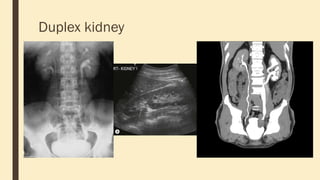

Duplex kidney

Horseshoe

kidneys